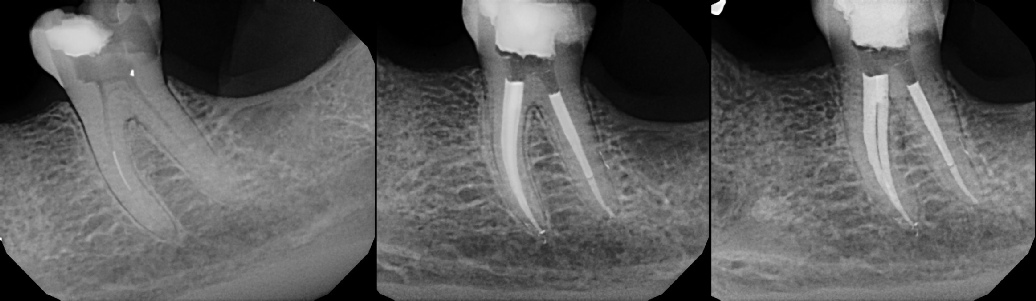

COMPLICATED ANATOMY LARGE LESIONS CALCIFIED CANALS PERFORATION / RESORPTION SEPARATED INSTRUMENTS SURGICAL CASES RETREATMENT / pOST REMOVAL OPEN APICES ACCESS THRU CROWNS Root Canal Case Portfolio

Pre-op Post-op 1 Post-op 2